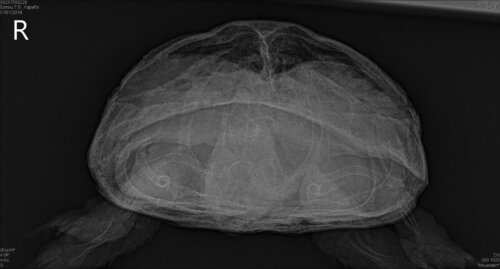

Вчера сделали рентген, на котором видно новообразование (7 месяцев назад его небыло). Ветеринар сказал заказать препарат саркомин, но его сейчас нет в продаже, может есть какие то аналоги, или кто то знает, где его можно купить? Чуть позже сегодня будет результат биохимии крови

по рентгену я не вижу новообразований.

У неё очень сжаты лёгкие, с большой вероятностью желудком и кишечником

Вот это сказали новообразование, вторая фотка рентген 7 месяцев назад

это больше похоже на каловый завал, но я подожду что наш герпетолог ответит

@Кристина14254 наш врач ответила, что по рентгену невозможно определить что именно там находится

По рентгену это может быть и киста на печени, и желудок набитый едой, и абсцесс… очень много вариантов

в таких случаях делают кт или мрт для уточнения диагноза.